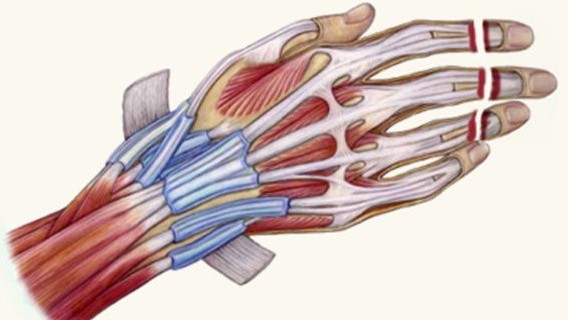

Bhat AK, Narayana Kurup JK, Acharya AM, Kumar B. Outcomes of radialization for radial longitudinal deficiency: 20 limbs with minimum 5-year follow-up. J Hand Surg Eur Vol. 2019;44(3):304-309.

Acharya AM, Ravikiran N, Jayakrishnan KN, Bhat AK. The role of pedicled abdominal flaps in hand and forearm composite tissue injuries: Results of technical refinements for safe harvest. J Orthop. 2019;16(4):369-376.